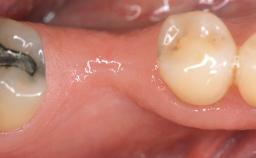

A 30-year-old woman was referred by her general dentist for evaluation of an esthetic complication related to previous implant treatment for congenitally missing maxillary lateral incisors. The patient’s chief complaint was the inadequate esthetic appearance of her smile. The case demonstrates the use of a combined approach to achieve optimal results. Two different flap designs - a tunnel technique and a coronally advanced flap - are employed based on the surgical objectives for the affected site.

Jaw Maxilla

Area Anterior